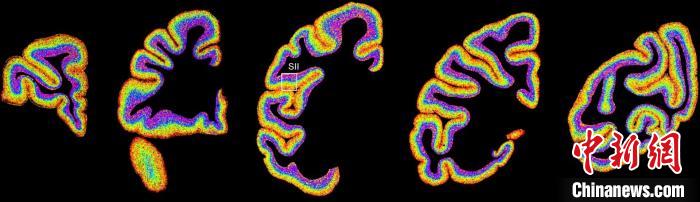

圖為不同類型細(xì)胞在獼猴大腦上的分布切片。 中國科學(xué)院腦科學(xué)與智能技術(shù)卓越創(chuàng)新中心 供圖

李澄宇說,科研人員做的事情好似“查戶口”,也就是搞明白猴腦里有哪些細(xì)胞、這些細(xì)胞在哪些位置。搞明白這些就形成了一個(gè)大的數(shù)據(jù)集,科研團(tuán)隊(duì)挖掘這個(gè)數(shù)據(jù)集,發(fā)現(xiàn)了很多有意思的現(xiàn)象:比如,興奮性神經(jīng)元、抑制性神經(jīng)元以及非神經(jīng)元在大腦皮層中的分布呈現(xiàn)明顯的特異性,也就是不同細(xì)胞“住”哪,有一定規(guī)律。